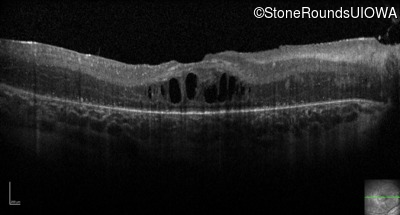

Optical Coherence Tomography - Right - 20/80

Exemplar / OCT Stack